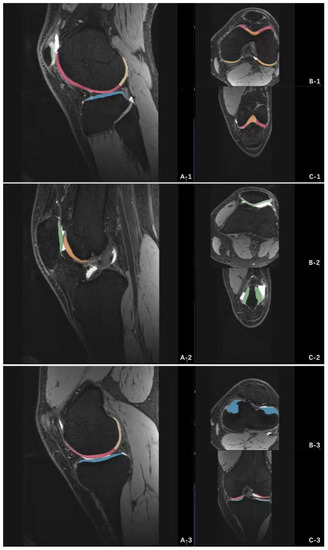

The MRI data of 3D-DESS sequence were imported into Siemens knee cap (version 1.5) workstation for automatic recognition of knee cartilage. The software could automatically divide articular cartilage into eight sub-regions [,]: patella (P), femoral trochlea (TrF), anterior area of lateral femoral condyle (aLFC), posterior area of lateral femoral condyle (pLFC), and anterior area of medial femoral condyle, (aMFC), posterior area of medial femoral condyle (pMFC), lateral tibia plateau (LT), medial tibia plateau (MT). The volume of cartilage in each subregion was obtained by manual fine-tuning. The aLFC and pLFC were divided by the posterior horn of the lateral meniscus, and the aMFC and pMFC were divided by the posterior horn of the medial meniscus. The specific operation interface of the software was shown in Figure 2, and the 3D model established by the software according to the preoperative knee cartilage of the patient is shown in Figure 3.

Figure 2.

Siemens knee cap (version 1.5) software 3D-DESS image workstation operation interface. The software can automatically recognize and calculate the volume of each cartilage subregion of the knee joint. (A-1), Sagittal position of lateral knee joint; (B-1), Horizontal position of lateral knee joint; (C-1), Coronal position of lateral knee joint; (A-2), Sagittal position of middle knee joint; (B-2), Horizontal position of middle knee joint; (C-2), Coronal position of middle knee joint; (A-3), Sagittal position of medial knee joint; (B-3), Horizontal position of medial knee joint; (C-3), Coronal position of medial knee joint.